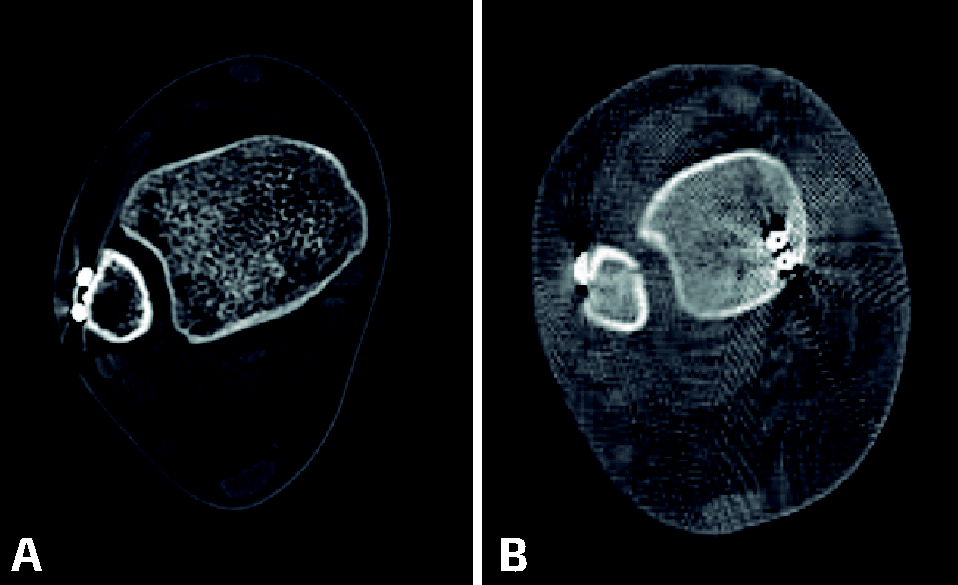

En el enfoque tradicional, los esfuerzos van encaminados a la consecución de una reducción anatómica y fijación interna estable de los maléolos lateral y medial, que se realiza en primer lugar. Tras ello, se aplican maniobras de estrés para evaluar la integridad de la sindesmosis, como el test de Cotton (tracción lateral del peroné) o la rotación externa forzada, observando si estas hacen aumentar los espacios claros medial o tibiofibular en la fluoroscopia(15,16). Si existe sospecha de inestabilidad, se procede a la reducción del peroné a la incisura mediante pinzas de reducción a compresión con control radiológico pero sin visualización directa, lo cual aumenta el riesgo de reducciones inadecuadas(17,18,19)(Figura 2).

Figura 2. Imágenes de tomografía computarizada. A: corte axial con reducción adecuada del peroné en la incisura; B: reducción inadecuada con incongruencia.

Marmor et al.(20) proponen descubrir una malposición del peroné según su apariencia fluoroscópica y la medida del espacio claro tibiofibular comparado con el miembro contralateral sano; un ensanchamiento del espacio claro tibiofibular y/o un peroné con forma de cuchara implican rotación interna fibular, mientras que la forma de cuchillo o un estrechamiento del espacio claro indican rotación externa.